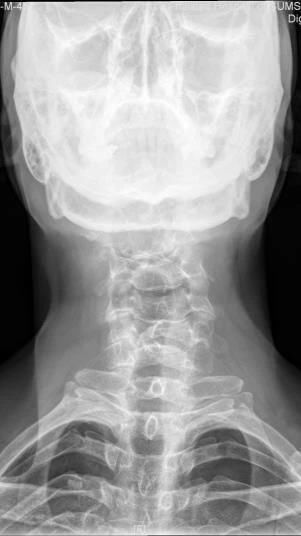

Case12:F,4y;患儿颈部活动受限1个月。

文章插图